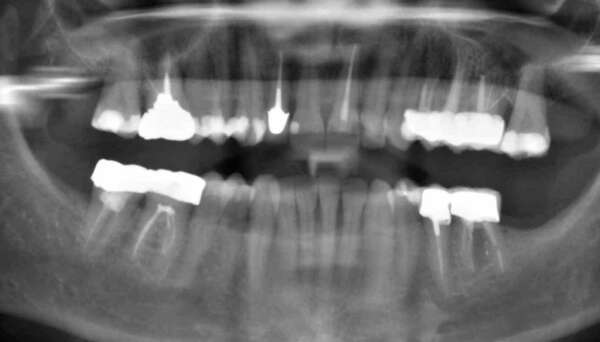

La mise en charge immédiate des implants et leur consolidation par la contention d'un bridge provisoire.

Un implant est composé de plusieurs pièces, usinées de façon très rigoureuse, et emboîtées successivement les unes dans les autres.